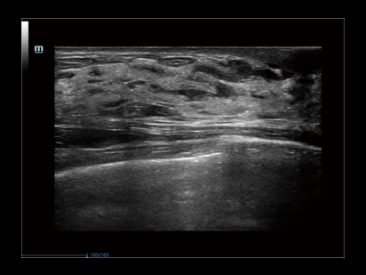

Przypadek kliniczny z wykorzystaniem technologii iClear: staw barkowy